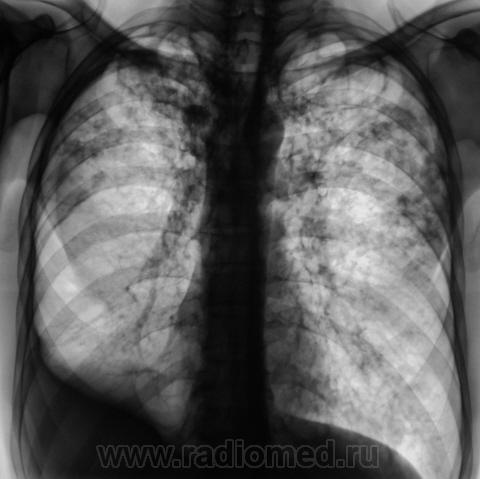

Мужчина, работает в областном центре, "в охране". Приехал проведать маму, так как мама заболела. На 3 день почувствовал себя "не очень" и решил обратиться в местную поликлинику к терапевту. В регистратуре выяснили, что мужчина в течение 3-х лет профилактическую флюорографию не проходил и направили во флюорографический кабинет.

Сразу-же, после производства флюорограммы, пациент был дообследован в рентгенодиагностическом кабинете согласно стандарту.

добрый день. мама как раз может и не болеть.а у ее сына хороший инфильтративный туб-з с распадом и обсеменением,но процесс не "свежий",есть объемное уменьшение в\д справа,нет перикавитарной инфильтрации,но активный. из вновь приобретенной патологии-экссуд.плеврит справа. немного удивляет:б-ой из области,скорее всего "обязательный контингент" ,и рфо более 3лет.иногда из иту приходят с меньшими процессами. в мокроте нашли куб?

1. Я выставил без "всяких" фиброзно-кавернозный. Далее коллеги-фтизиатры разберутся.

Фтизиатры согласились с ФКТ, палки при микроскопии - море.